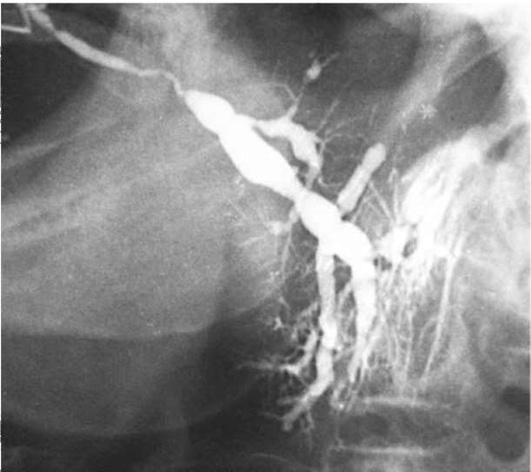

Пороки развития выводных протоков слюнных желез выявляются на сиалограммах в виде их значительного расширения (эктазии). Наиболее часто расширяются околоушной (рис. 6.1) или поднижнечелюстной протоки, что приводит к развитию хронического сиаладенита или слюннокаменной болезни. Нередко встречаются дивертикулы протока в виде ограниченного слепого выпячивания его стенки (рис. 6.2). Если таких дивертикулов очень много, то речь идет о хроническом паренхиматозном паротите или сиалодохите.

Рис. 6.1. Кистообразное расширение околоушного протока слева